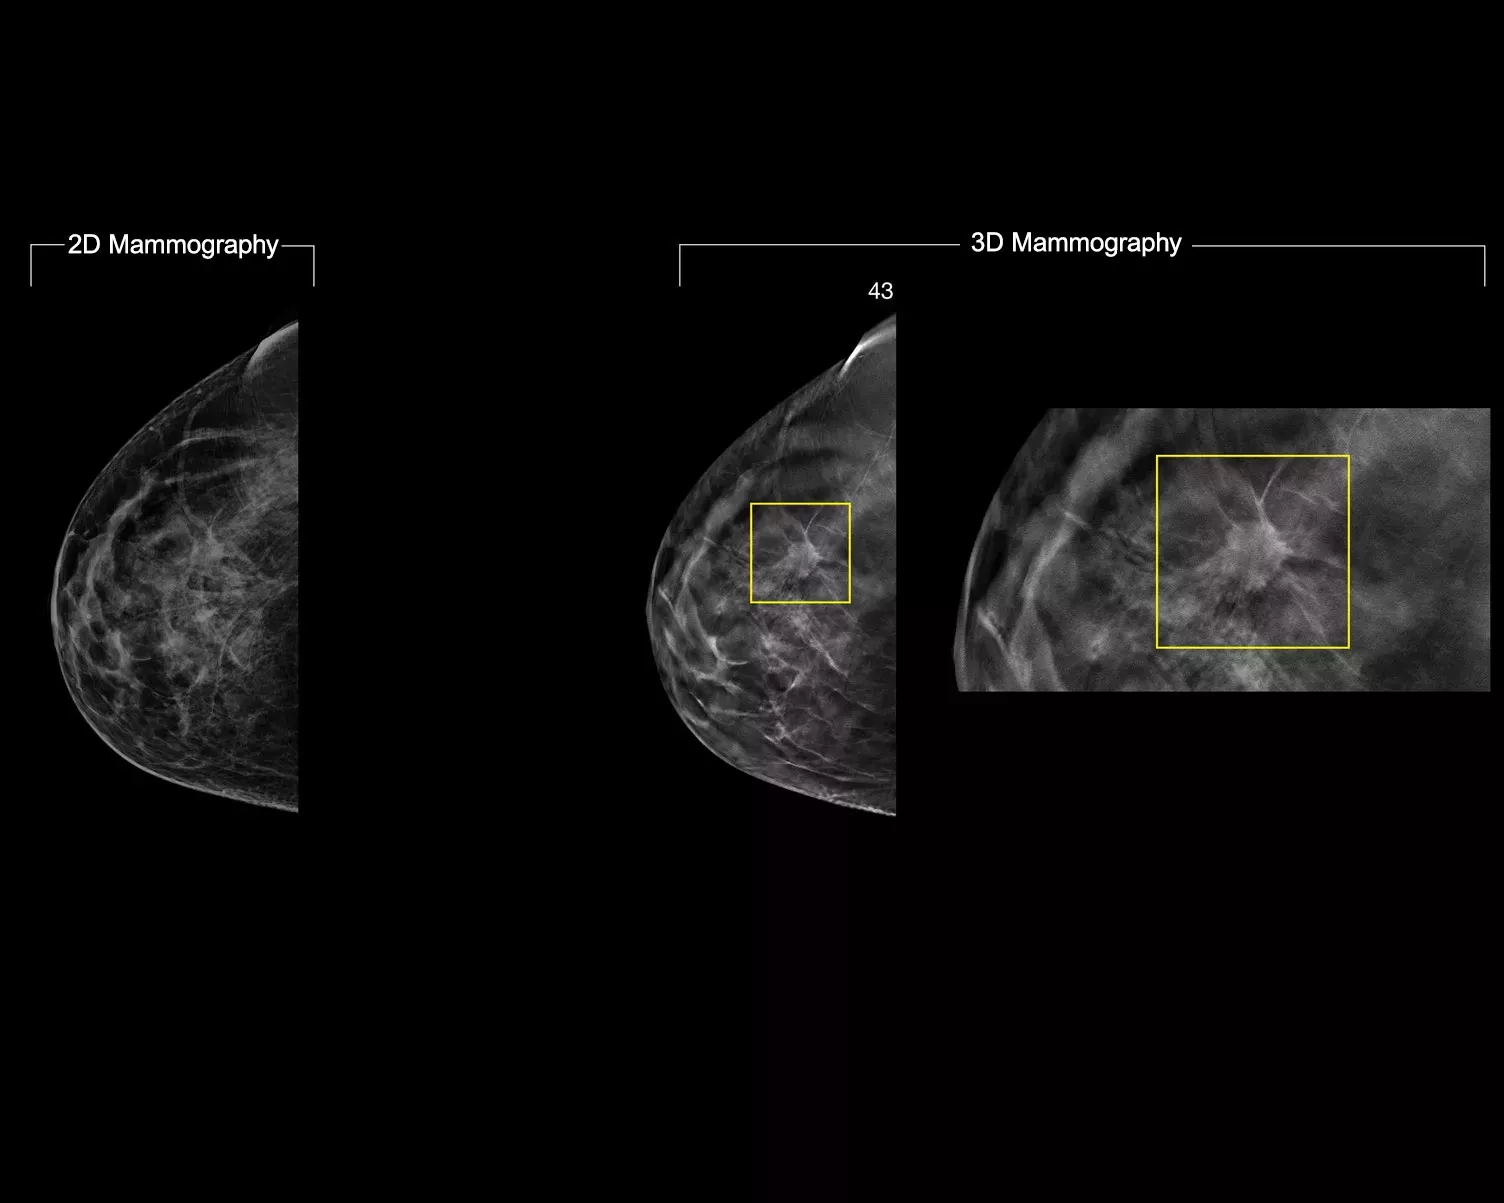

ImageChecker 2D CAD Technology searches digital mammograms for potential microcalcifications and masses, characteristics commonly associated with breast cancer.

• Regions-of-interest are highlighted for the radiologist’s attention

• Delivers highly sensitive results without excessive false-positive marks, streamlining case review2

• Easy navigation to the slice of interest in the tomosynthesis stack, when used in combination with Smart Mapping on synthesized 2D images

Digital mammography with peer emphasize marks